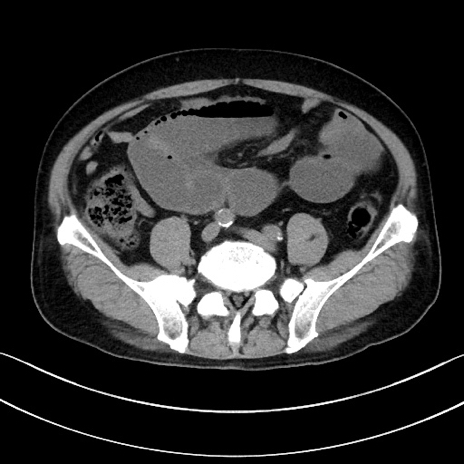

冠状断像

【症例】70歳代男性

【主訴】腹痛

【現病歴】今朝から腹痛あり。全体的に痛い。特に左上の方。排ガスが今日はない。冷や汗が出る。

【既往歴】直腸癌術後

【身体所見】左側腹部〜上腹部に圧痛あり。腹膜刺激症状明らかなではない。軽度反跳痛。左下腹部に術後瘢痕あり。

【データ】WBC 7700、CRP 0.02